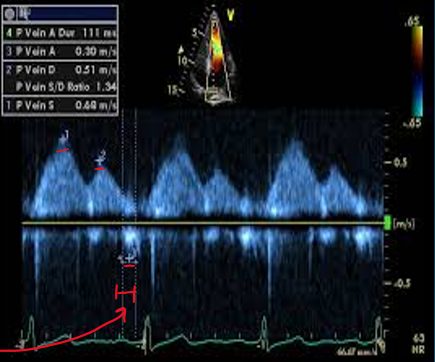

what clinical measurements are done with pulmonary venous flow?

peak systolic velocity (PVs)

peak diastolic velocity (PVd)

peak atrial reversal velocity (Pva)

duration of pulm vein atrial reversal (a-dur)

what are indications of elevated LV filling pressures?

e/e’ ratio

Pva

pulm a-dur vs mitral valve a-dur

pulm venous systolic flow vs pulm venous diastolic flow

e/e’ ratio >15

Pva >.35 m/s

pulm adur 20ms > than mitral a-dur

pulm venous syst flow < pulm venous diastolic flow